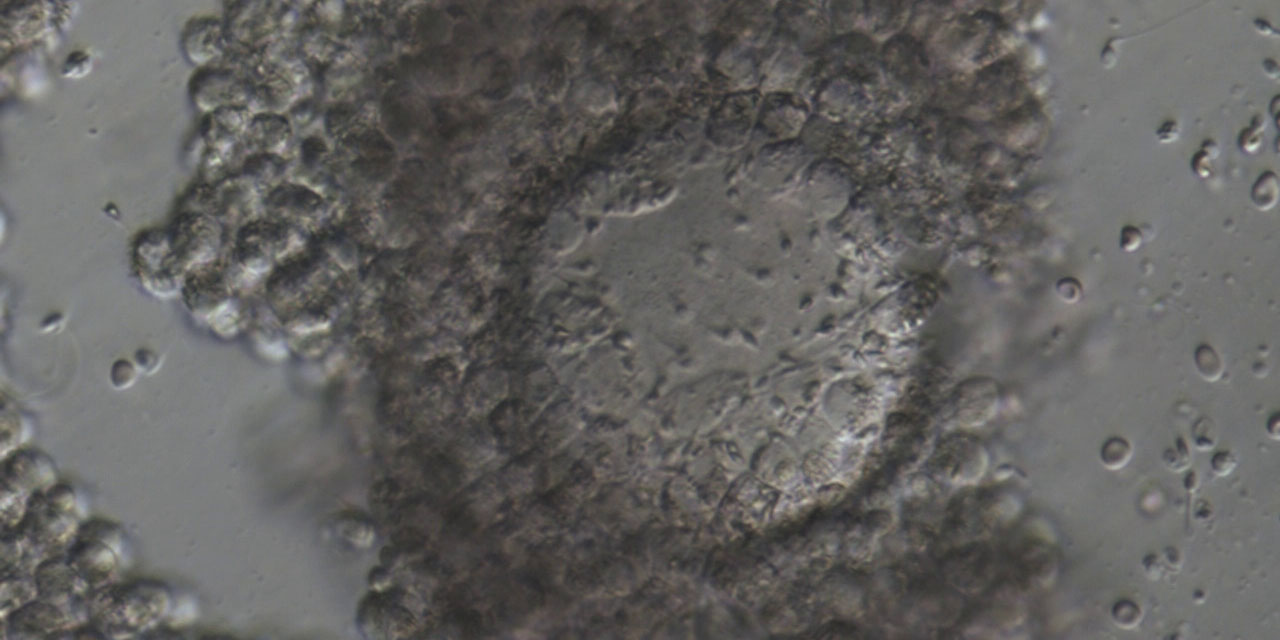

Forscher und Kliniker versuchen durch eine optimale Unterstützung des Embryos vor der Implantation die Schwangerschaftsrate, sowie die Geburtenrate zu erhöhen. Es ist aber nicht nur wichtig den Embryo optimal zu unterstützen, sondern ebenso wichtig dem Embryo keinen Schaden zuzufügen. Dies gilt auch für die verwendeten Kulturmedien, die keinen Einfluss auf den normalen Ablauf der frühen Embryo-Entwicklung haben sollten. Ziel unserer Untersuchungen ist es, den Einfluss von GM-CSF, supplementiert in einem menschlichen ART-Medium oder in einem mausoptimierten Medium, auf die Zellzahl und die Zelllinien im frühen Präimplantation-Embryo der Maus zu analysieren.

In unserer Untersuchung nahmen wir an, dass unterschiedliche Konzentrationen von GM-CSF einen Einfluss auf die Entwicklung des Trophectoderms und die Entwicklung der Plazenta haben könnten. Das Ziel dieser Studie ist die morphologische Untersuchung von Plazenten von Mausfeten, nachdem die Embryonen in Medien mit dem Wachstumsfaktor GM-CSF kultiviert wurden.